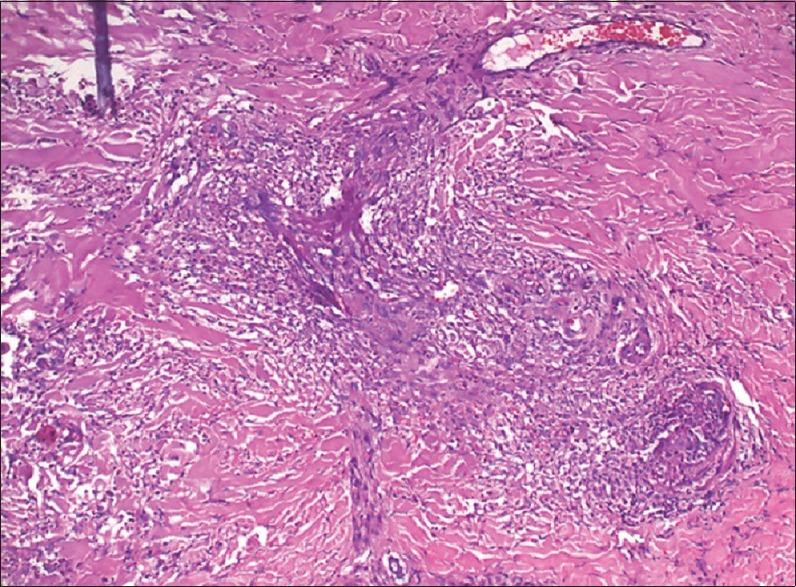

A 47-year-old male with acquired immune deficiency syndrome (AIDS) presented with multiple hyperpigmented papules and nodules on both ankles, dorsum of bilateral feet and soles. It was associated with mild itching and pain. The patient was diagnosed with human immunodeficiency virus (HIV) in 2007. First-line antiretroviral therapy (ART) was started in 2009 to which he responded initially. He was shifted to second-line ART 11 months ago in March 2015 due to treatment failure as suggested by CD4 count of 50 cells/mm(3). The present skin lesions started 2 months after the initiation of second-line ART. Differential diagnoses considered were Kaposi's sarcoma and immune reconstitution inflammatory syndrome (IRIS) related infections, but biopsy was suggestive of erythema elevatum diutinum (EED). Patient was started on oral dapsone 100 mg/day and increased to 200 mg/day to which he is responding gradually. In the present case, appearance of the lesions after initiation of second-line ART coupled with increase in CD4 count and decrease of viral load below undetectable level suggest that EED could be an IRIS.

一名47岁的获得性免疫缺陷综合征(艾滋病)男性患者,双侧脚踝、双足背及足底出现多个色素沉着性丘疹和结节,伴有轻度瘙痒和疼痛。该患者于2007年被诊断为人免疫缺陷病毒(HIV)感染。2009年开始一线抗逆转录病毒治疗(ART),最初治疗有效。因CD4细胞计数为50个/立方毫米提示治疗失败,于2015年3月(11个月前)转用二线ART。目前的皮肤病变在开始二线ART后2个月出现。鉴别诊断考虑为卡波西肉瘤和免疫重建炎症综合征(IRIS)相关感染,但活检提示为持久性隆起性红斑(EED)。患者开始口服氨苯砜,初始剂量为100毫克/天,后增至200毫克/天,病情逐渐好转。在本病例中,二线ART开始后病变出现,同时CD4细胞计数增加且病毒载量降至检测不到水平,提示EED可能是一种IRIS。